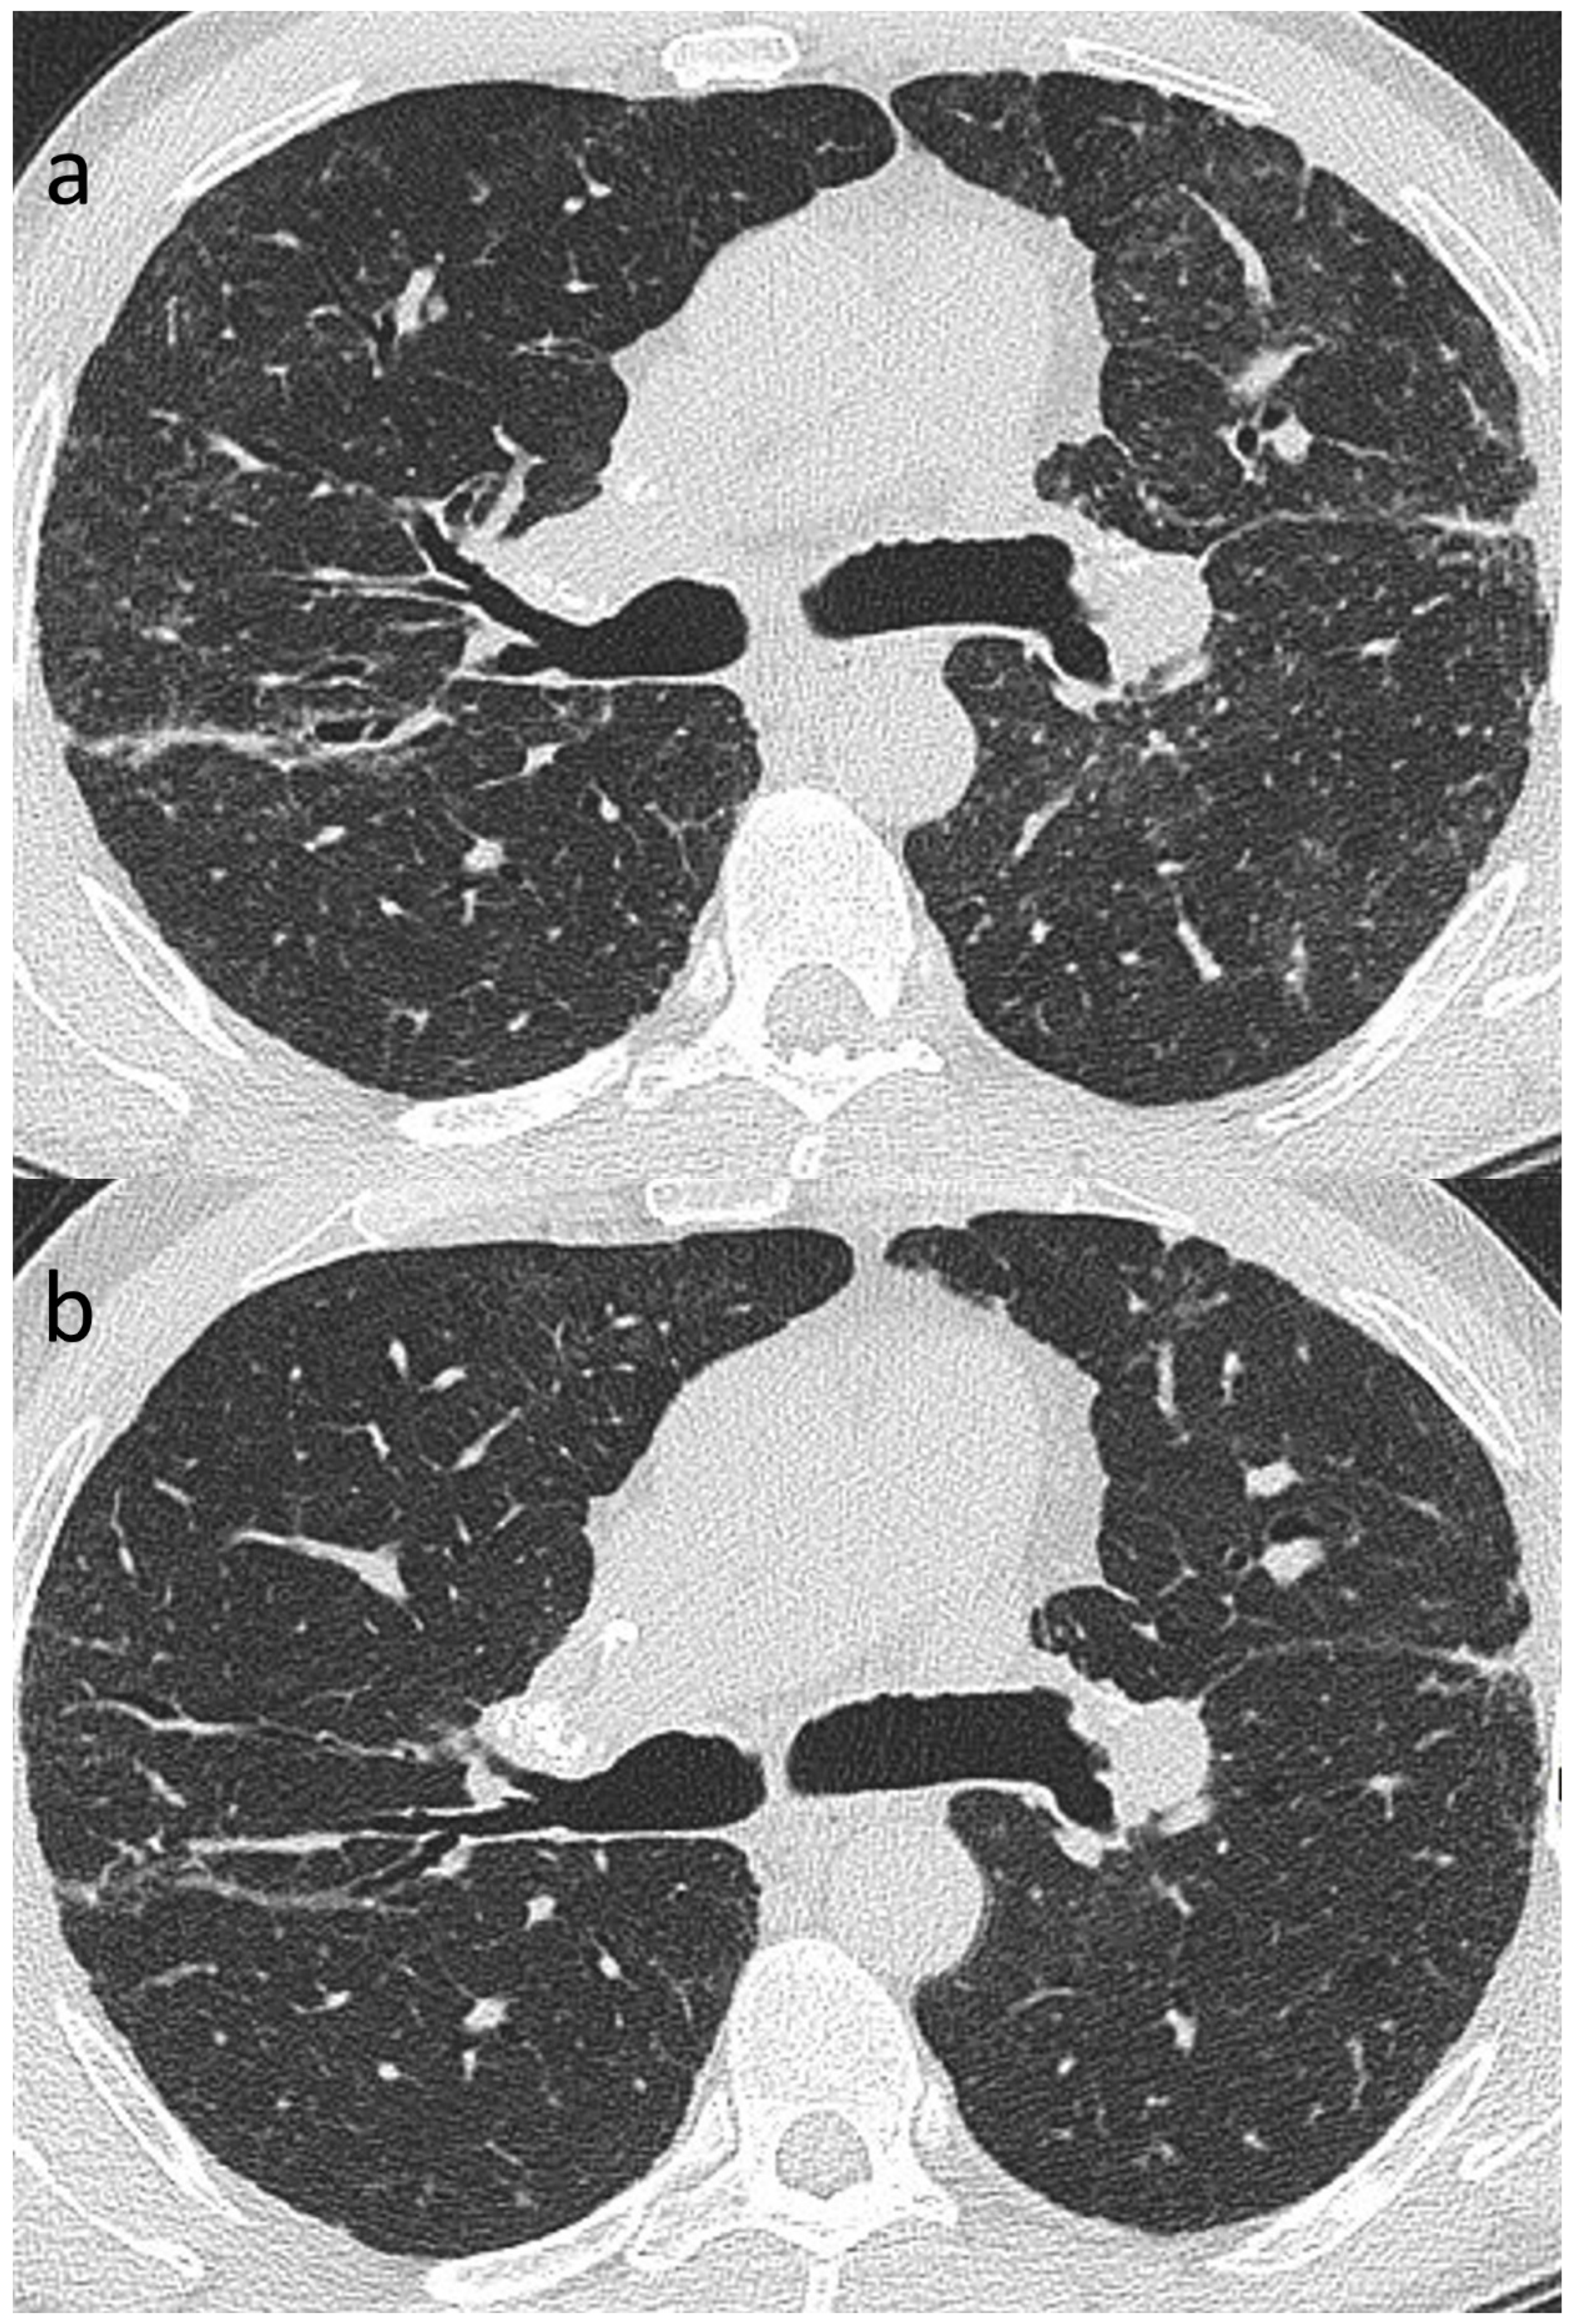

7.2. Reversible, Irreversible and Progressive Disease in Sarcoidosis

Of the variety of CT patterns reported in sarcoidosis, nodular infiltrates are most likely to improve or resolve at follow-up [41]. Additionally, peribronchovascular thickening, consolidation and ground-glass opacification also have the potential to resolve completely [41,49,130], particularly with treatment [49] (Figure 8a,b). While linear opacities may clear, Murdoch and co-workers found an increased likelihood of progression over time and more so than with other morphologic features [41]. The natural history of ground-glass opacities is more difficult to predict and this CT pattern is a poor predictor of both disease activity and prognosis [41,49]. In part, this might be due to the non-specificity of CT ground-glass opacification which might indicate ‘active’ (and therefore potentially reversible) granulomatous inflammation or irreversible fine fibrosis below the limits of CT resolution [50]. CT abnormalities tending to indicate irreversible disease include reticulation, architectural distortion, honeycombing and traction bronchiectasis/bronchiolectasis. However, while some patients inevitably progress despite treatment, relative stability over time is more common in sarcoidosis-related ILD than in overtly progressive fibrotic DILDs [108].

Figure 8.

(a,b): Reversible disease in sarcoidosis. Targeted images of the left mid-zone showing the resolution of multiple random micronodules over time in (a) 2015 and (b) 2017.